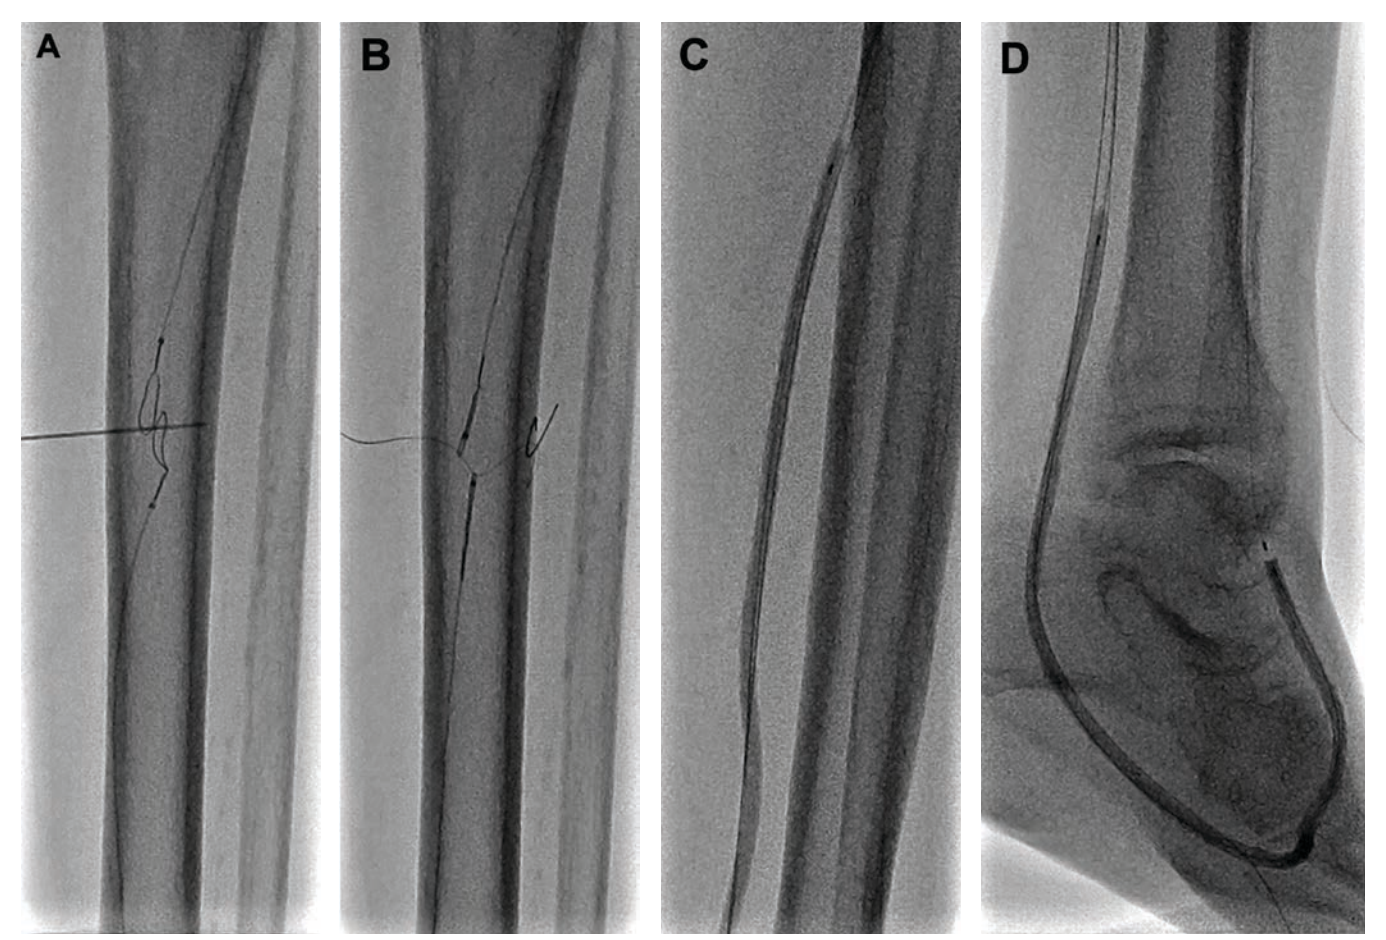

- Percutaneous Deep Vein Arterialization Using Zero Iodinated Contrast Technique for Limb Salvage in a Patient With Kidney Transplant and Impaired Renal Function

When contrast use isn’t an option, limb salvage may still be possible. This case highlights successful deep venous arterialization performed with zero iodinated contrast

in a patient with no-option CLTI and advanced renal disease—resulting in durable wound healing at 2 years. A compelling example of how CO₂ angiography and intravascular imaging can expand options for the highest-risk CLTI patients.